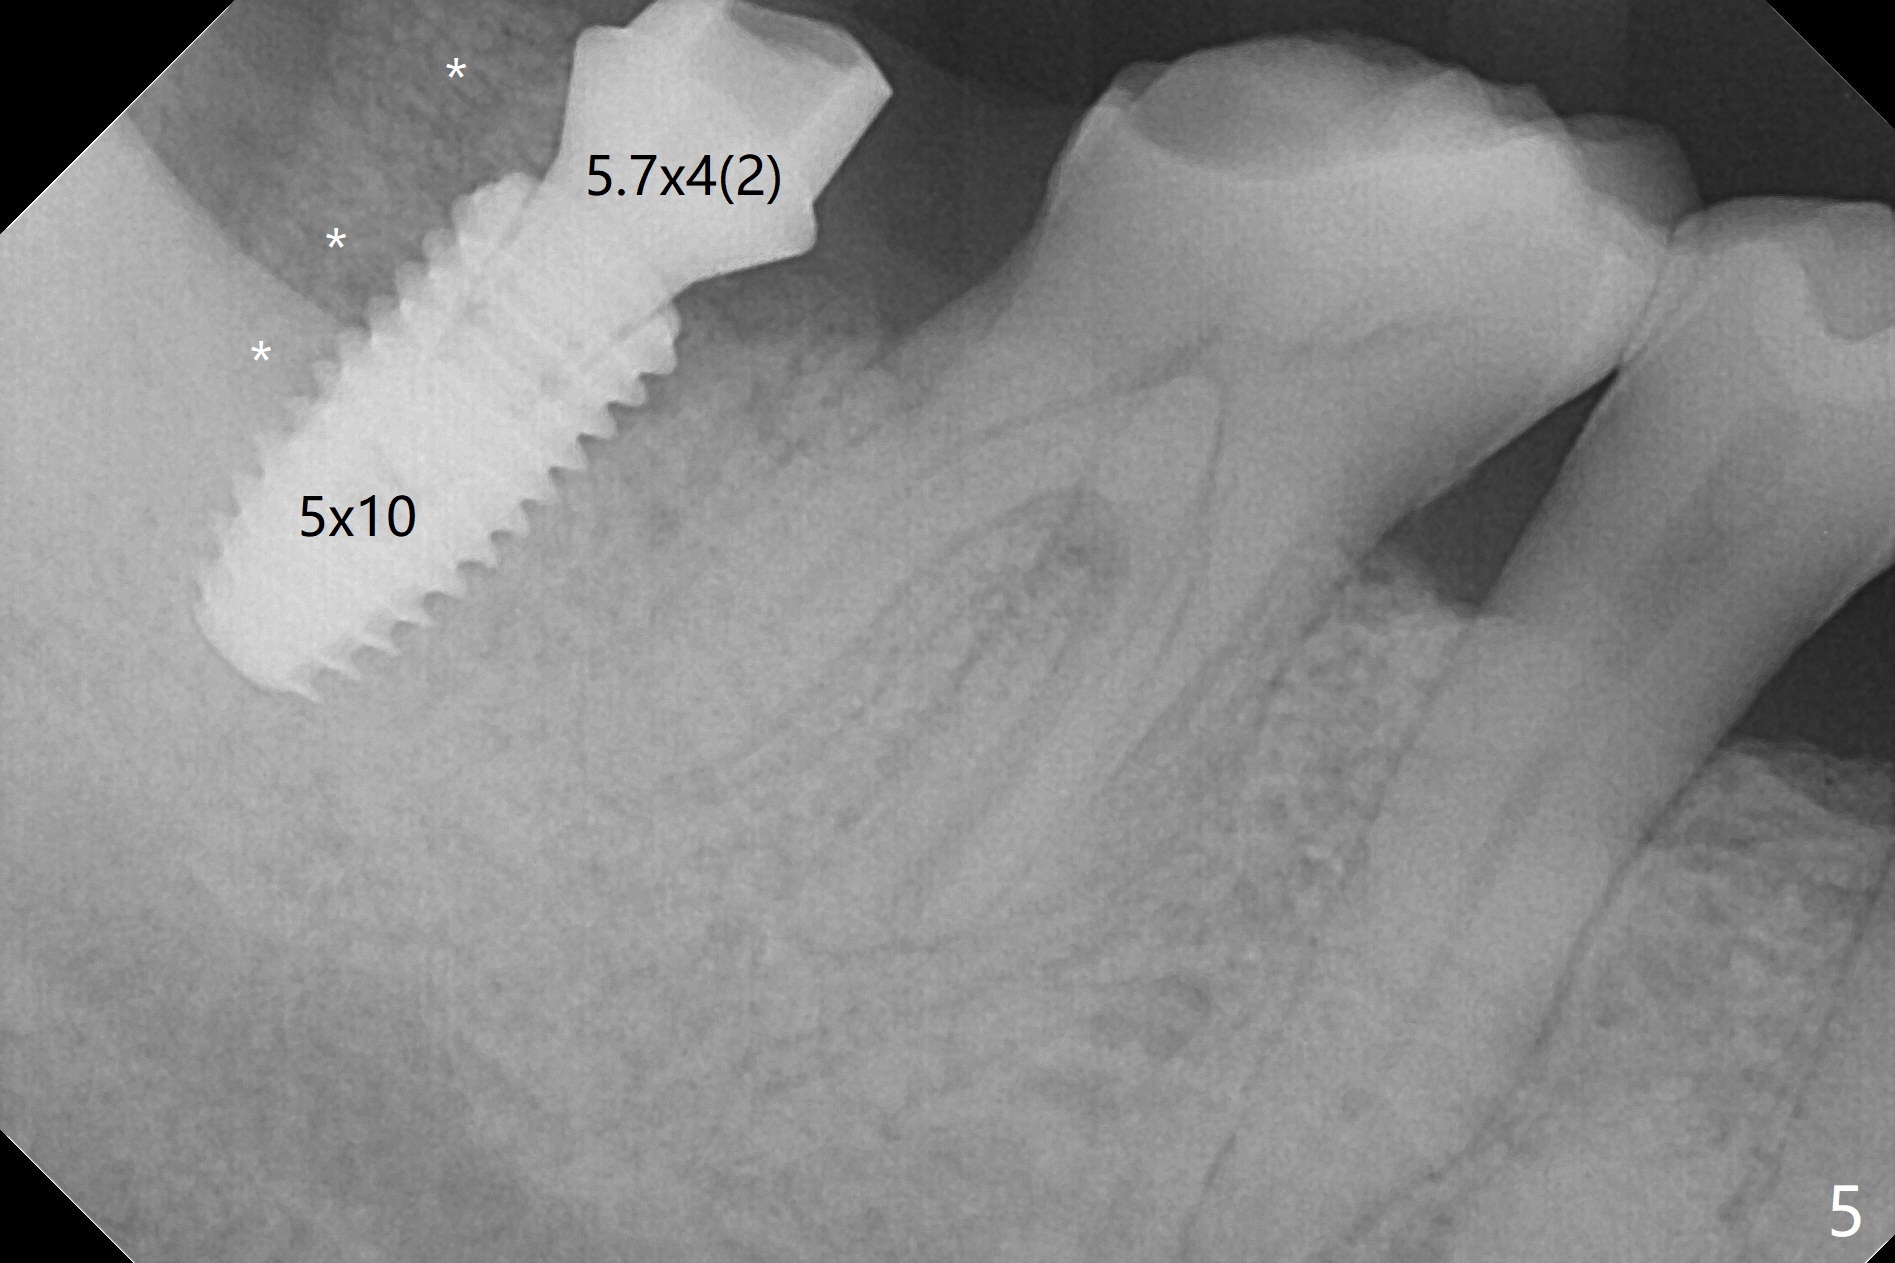

The residual roots of the tooth #31 are lower buccal (Fig.1 B), which in fact is molded and worn by the supraerupted tooth #2. When the tooth is extracted (Fig.2) and an implant, abutment (Fig.3 gold colored) and allograft (*) are placed, the abutment has to be trimmed. An atypical immediate provisional is fabricated by spreading setting acrylic over the abutment and bone graft (Fig.4 P) with occlusal equilibrium. Advantages of the guided surgery are good position (Fig.3 buccolingual), trajectory and depth (Fig.5,6) of the implant. The buccodistally exposed implant threads are packed with allograft in sufficient amount (Fig.3,5,6 *). The atypical immediate provisional breaks down and dislodges 3 weeks postop (Fig.7). In fact the implant plateau is exposed buccally. A monojet is given to the patient for self cleansing. He is instructed to return in 3 weeks. The exposed implant threads are covered 1.5 months postop (Fig.8). Incomplete abutment seating (Fig.9 <) was not noted until 1 year 3 month post cementation when the crown was mobile (Fig.10). A 6x3 mm healing abutment is placed. Three days later, the crown is sectioned and separated from the abutment. The latter returns to place; due to angulation associated with PA, the gap between the implant and abutment is indistinct (Fig.11). Bitewing is taken; the gap exists (Fig.12 <). The abutment seems to be seated deep; there is apparently soft tissue interference. A 5.2x4(2) mm abutment remains incompletely seated (Fig.13 >). A 5.2x4(3) mm one is completely seated (Fig.14 <). Zirconium crown with an access hole is cemented in the mouth. The crown and abutment is then removed for residual cement removal and reseated and torqued (Fig.15). Four months later, the Zirconium crown is fractured (Fig.16). Impression is retaken for high noble metal crown without access hole for strength (Fig.17).